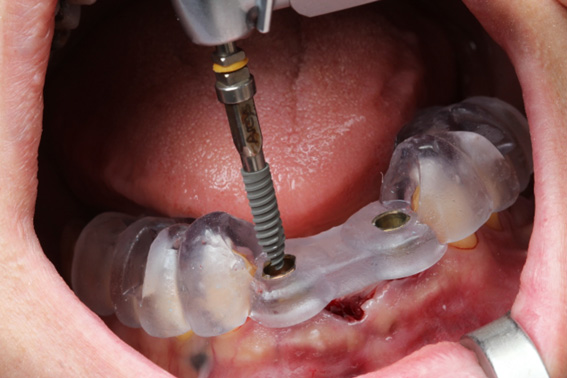

5 | Implant Installation using the Arcsys Guided Surgery System

6 | Installation wrench stopper in contact with the sleeve